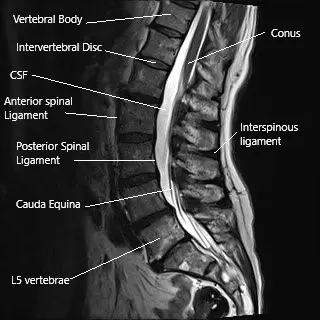

The spinal cord runs in the vertebral canal and gives numerous branches (spinal nerves) as it travels down the canal. The vertebral canal is formed by the vertebrae stacked upon each other. The lamina creates the vertebral canal’s roof, and the vertebral body forms the floor.

The spinous process is a bony projection at the back of the vertebrae. The projections may be felt under the skin as you run your hand in the lower back’s midline. The spinous processes provide stability and help in the backward movement of the spine.

MRI of the lumbar spine showing the interspinous ligament and the spinous process.